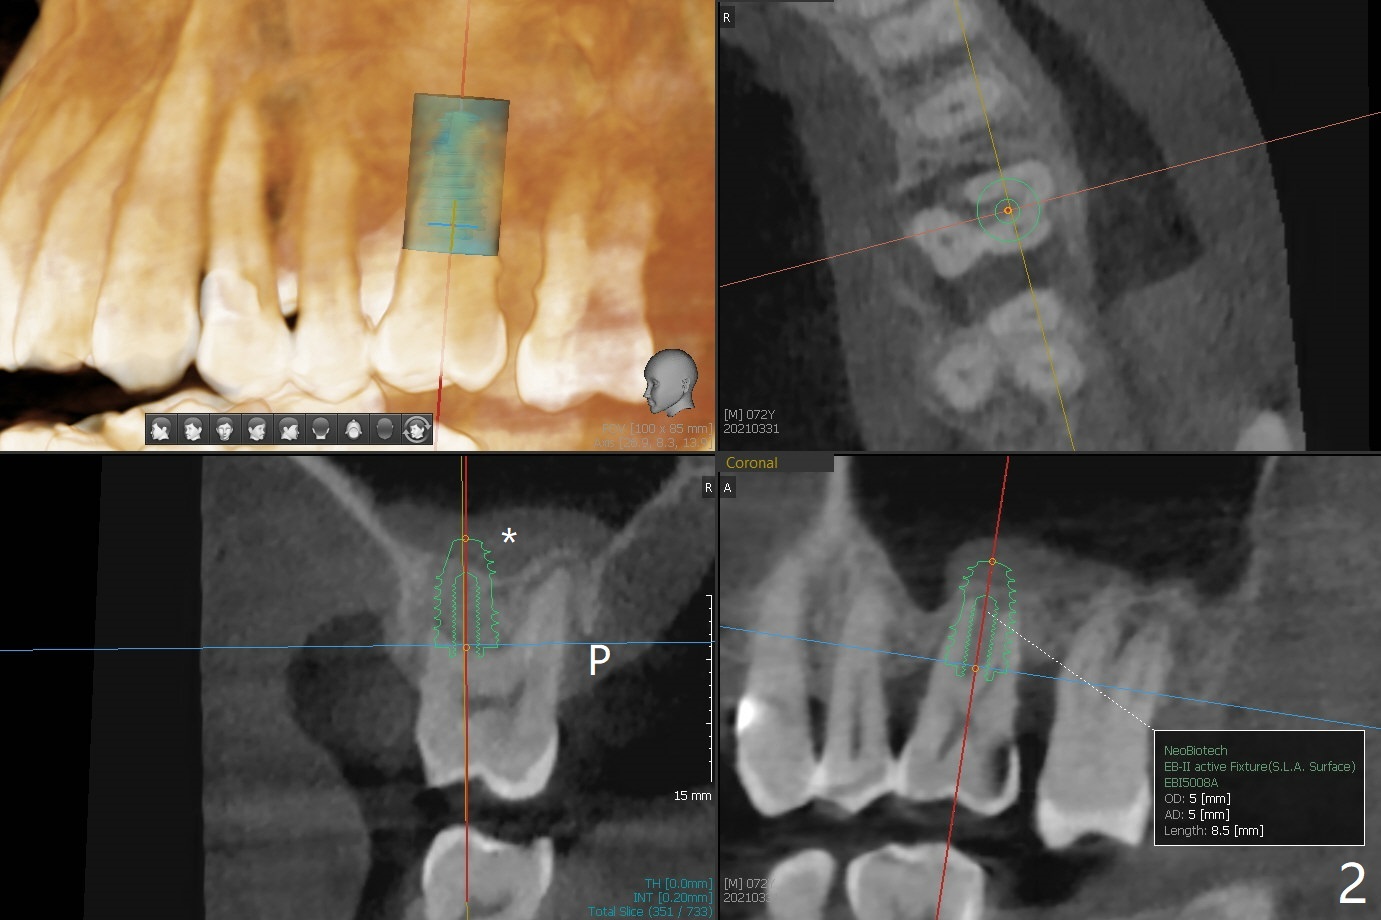

A 72-year-old man agrees to have #14 to be extracted for implant (Fig.1). In the first stage, impression is taken for #14 and 18 implant placement with guide. Due to odontogenic sinus infection (Fig.1,2 *), Z pack will be taken to prevent implant infection associated with sinus lift (Fig.2). Remove provisional and abutment once the sockets heal. To combat #15 supraeruption, the implant at #18 will be placed deep; if the torque is high, place a large diameter healing abutment or provisional with large base will be fabricated so that a short cuffed abutment will be used for final restoration. Heavy occlusal reduction at #15 will be conducted (Fig.3 curved lines). In spite of the fact that the bone height at #3 is 3-4 mm, the sinus floor is flat (Fig.4). Internal sinus lift is not expected to be too difficult. Use Magic Sinus Lifter, followed by implant placement at the same stage (Fig.5,6).